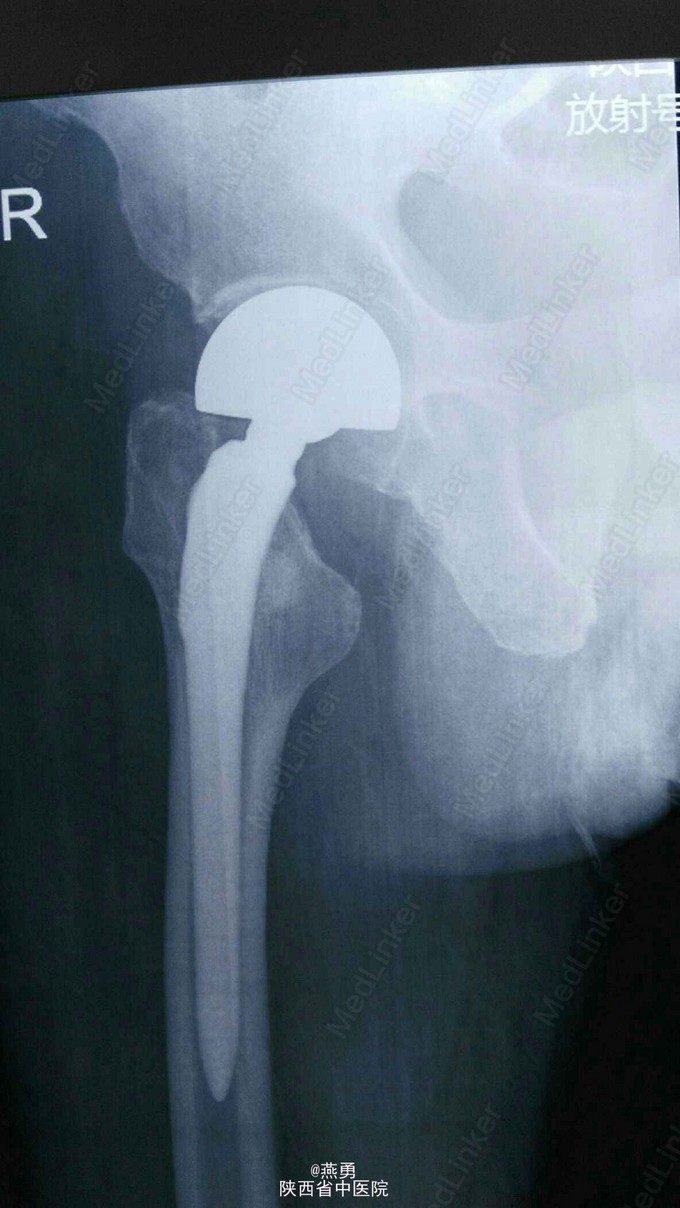

诊断:右股骨颈骨折,骨囊肿待查。治疗:右侧人工股骨头置换术,病灶清除探查术。麻醉生效后,常规逐层切开及暴露可见股骨颈颈中型骨折,清除周围纤维增生挛缩及瘢痕组织,取头器取出断裂的股骨头,患肢内收外旋脱位后,截骨,髓腔开口及扩髓,探针可见小转子内测约0.5*0.8cm病灶空腔,内壁完整,刮除腔内病灶送病检,填入少量抗生素型骨水泥,装入生物型股骨柄,置入双动头股骨头假体,复位,见右侧髋关节屈伸旋转活动良好,未出现脱位,双下肢等长。冲洗,清点纱布器械后,放置引流,关闭伤口加压包扎。 术后安返病房行预防感染预防血栓及对症治疗。

术后给予预防感染,抗炎,镇痛,消肿治疗。常规拍片复查,密切跟进并观察。